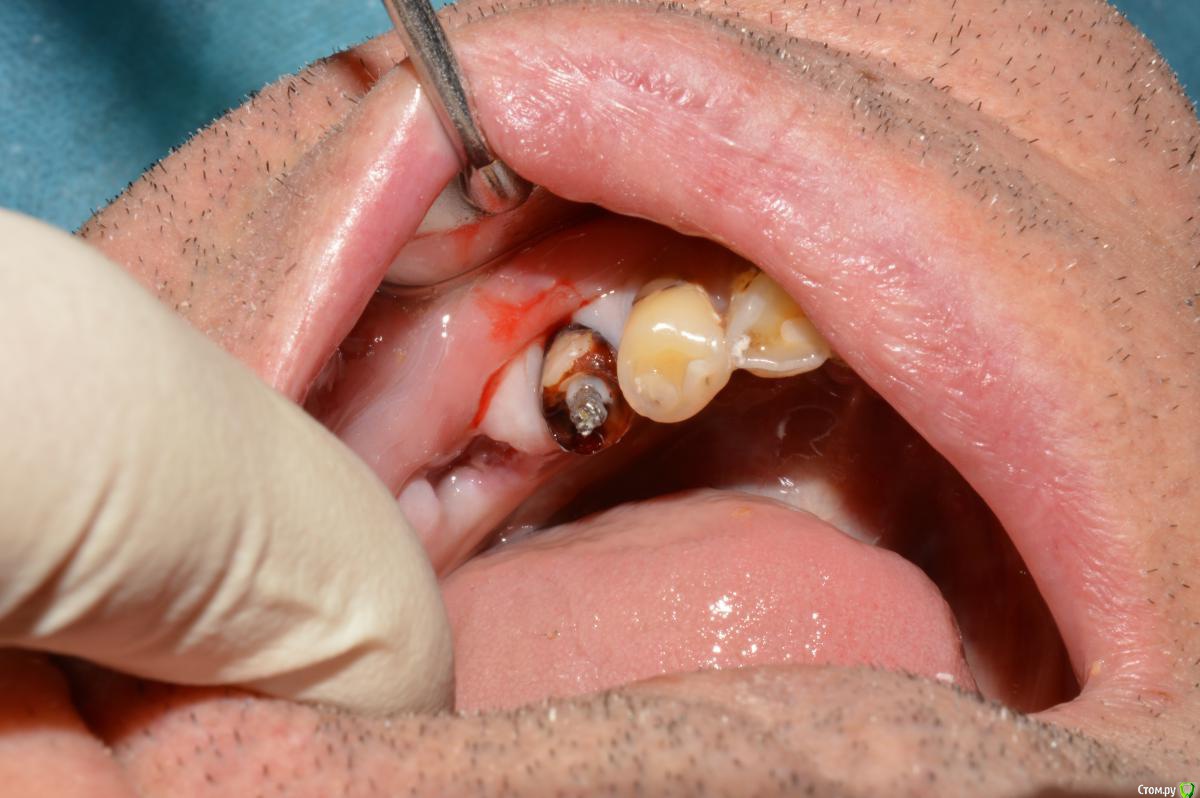

Елена509 Опубликовано 19 ноября, 2015 Поделиться Опубликовано 19 ноября, 2015 Доктора, помогите, пжл, ситуация какая - ортопед направил для удаления штифта и перепломбирования к.к 35, начали - анестезия, выудили штифт, начали расширять, уперлись на 15 мм, пошли на снимок с гутт штифтом(прилагается), недолет, вернулись, сразу прошли дальше, по апексу -18мм, убавила до 17,5, мастер штифт - 35, латералка, пошли на контроль, а там - загнутый штифт за верхушкой(рг прилагается), вернулись, все вытащила, загнутый тоже(95% - я его прям признала), отмыли просушили, по апексу те же 18мм, примеряю мастер штифты все как то не так встает, в итоге 70 подогнала, на те же 17,5 мм, поставила, с латералкой, идем на контроль, там вот такая вот фигня(рг - "последний"), вопросы - это что, невытащеннный гут.штифт или на его место эпоксидка затекла? что с прогнозом и что делать? 1 Ссылка на комментарий

Л Ю С Я Опубликовано 20 ноября, 2015 Поделиться Опубликовано 20 ноября, 2015 Здесь явная резорбция апекса, поэтому локатор мог показывать неправильно. В таких случаях делайте снимок с финишным файлом, где он? Ориентируйтесь больше на рентгенологическую длину, после лечения может произойти ещё небольшая убыль апекса, поэтому пакуйте -0,5, лучше мта. Какой билдап планируется в зубе? И вообще надо рассматривать картину восстановления окклюзии в целом 1 Ссылка на комментарий

Л Ю С Я Опубликовано 20 ноября, 2015 Поделиться Опубликовано 20 ноября, 2015 Под вкладку корень короткий, учитывая соотношение коронка/корень+ в апексе должно быть не менее 3-4 мм пломбировки. Посмотрите сколько там кости осталось, вывихнется все нафиг. Сделайте качественно эндо, а Отвечать за дальнейшую судьбу зуба ортопед будет скорее всего)))) Ссылка на комментарий